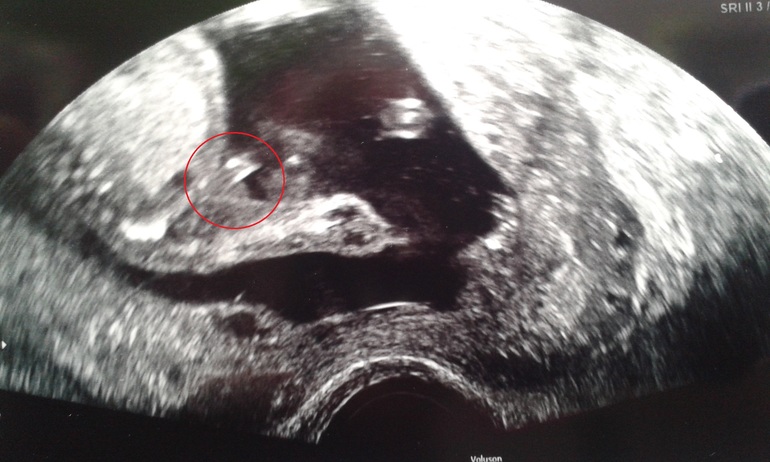

тут,если не понятно-стрелочкой на достоинство указала между ножек

а на этой в 26 неделек,лягушоночек,попка моя сладкая и "нечто"между ножек.Это мужчина??)

в каком именно?На верхнем в левом углу только ножки,как знак "равно",и между ножек выпуклость,а на нижнем только попка(прям четко две ягодички) с согнутыми ножками и висящим между ними "нечто")